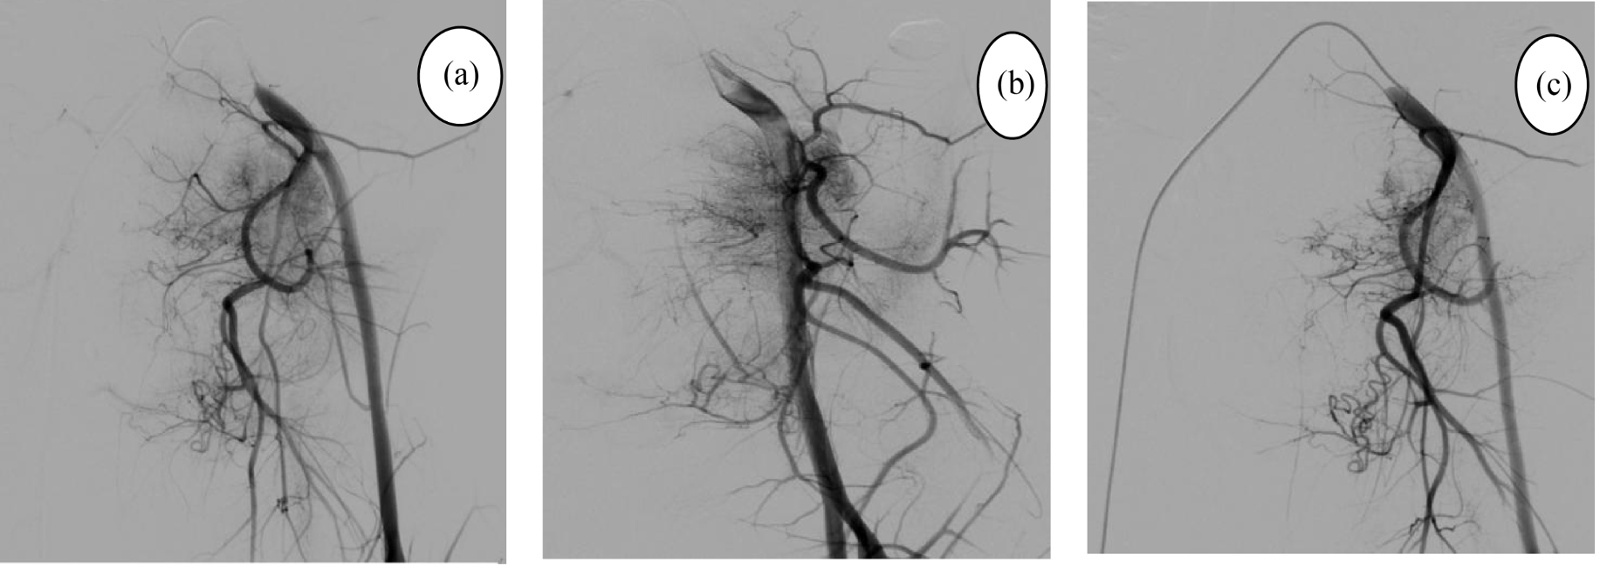

患者,男,10岁,因“下腹部持续性胀痛2周”入院。查体:下腹部压痛、反跳痛及肌紧张,肠鸣音减弱。实验室检查提示糖类抗原125 (CA125)升高至61.31 U/ml,血红蛋白进行性下降(由107 g/L降至76 g/L)。全腹CT平扫示腹膜后巨大混杂密度肿块,大小约8.5 cm × 9.7 cm × 8.0 cm,边界欠清,内见低密度区及斑片状高密度影(图1(a)),肿块推挤左侧输尿管致左肾轻度积水。增强扫描动脉期边缘实性成分轻度强化(图1(b)),静脉期强化程度略增加,内见无强化液化坏死区(图1(c)),肿块包绕左侧髂内动脉,管腔未见狭窄(图1(d))。影像学初步诊断为:腹膜后恶性占位伴出血。为明确诊断,行CT引导下腹膜后肿块穿刺活检,镜下见大量血凝块及少许炎性细胞,未见明确肿瘤细胞。结合临床及影像学表现,仍高度怀疑恶性肿瘤。经多学科综合小组(MDT)讨论认为,肿瘤巨大、血供丰富且与重要血管关系密切,一期手术切除难度高、术中出血风险极大,决定先行介入动脉栓塞术。数字减影血管造影(DSA)示左侧髂内动脉及其分支为肿瘤主要供血动脉(图2(a)图2(b)),遂超选择性插管至其分支,采用350 μm明胶海绵颗粒栓塞,术后造影显示肿瘤染色范围显著减少(图2(c))。随后在全麻下行“腹膜后肿瘤切除术 + 双侧输

(a),(b):栓塞前左侧髂内动脉造影见肿瘤染色丰富;(c):明胶海绵颗粒栓塞后造影见肿瘤染色减少。

Figure 2. The above images demonstrate the patient’s pre- and post-operative digital subtraction angiography (DSA) images

2. 术前术后数字减影血管造影(DSA)图像

影像学检查在腹膜后eRMS的全流程管理中至关重要,贯穿于定性诊断、临床分期、治疗方案制定、疗效评估及随访监测[7]。本例CT平扫腹膜后巨大混杂密度肿块(图1(a)),稍高密度区提示瘤细胞密集或急性出血,内部低密度区为坏死或陈旧出血;增强后肿瘤边缘实性成分轻中度强化,中央黏液基质及囊变坏死区无强化(图1(b)~(d)),并见左髂内动脉“血管包绕征”及输尿管侵犯致肾积水。DSA进一步证实其富血供特性(图2),为术前超选择性栓塞提供了依据。笔者结合本病例并复习相关文献[11] [12],总结腹膜后eRMS影像学特点:(1) 体积较大(直径常>5 cm),类圆形或分叶状,边界不清,呈浸润性生长;(2) CT平扫呈等或稍低于肌肉密度,因囊变、坏死或出血而密度混杂;MRI呈T1WI等或稍低信号(出血时呈高信号),T2WI不均匀高信号,DWI呈高信号;(3) 增强呈“葡萄簇”或环形强化,即边缘强化明显而内部富含黏液基质区无强化;(4) 易包绕或侵犯邻近大血管及输尿管等。(5) 可伴腹膜后淋巴结转移及远处(肺、肝、骨)转移。值得注意的是,RMS各组织学亚型间影像学表现无明显差异。